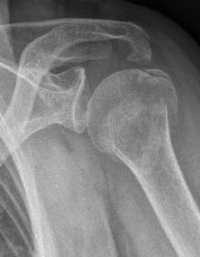

Picture: The subcapital humeral fracture shown here in the axis is not broken and only slightly bruised, so that a conservative therapy is possible. The left image shows the follow-up after 3 weeks. The patient has already started physiotherapy. The x-ray shows an increase bone healing.